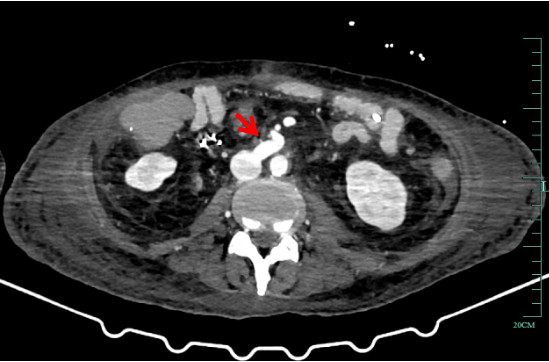

患者二次移植术后感染风险高,术后予美罗培南1 g /8 h静滴、更昔洛韦250 mg/12 h静滴、复方磺胺甲噁唑片0.48 g BIW鼻饲、万古霉素500 mg /8 h静滴、伏立康唑200 mg /12 h微泵维持和卡泊芬净50 mg /d(首次剂量70 mg)静滴抗感染。结合腹水、静脉血和引流液培养结果及药物浓度调整抗感染方案,结合患者感染指标逐步停用抗感染药物。他克莫司2 mg, 2次/d鼻饲抗排异,根据他克莫司药物浓度调整用量,第1个月为15~20 ng/mL,6个月内为10~15 ng/mL,之后为8~10 ng/mL[6]。第1天免疫球蛋白25 g, 1次/d静滴,继续使用3~5次至他克莫司达到治疗水平。甲泼尼龙降阶梯治疗,护肝护胃化痰肠外营养支持,每周两次肠镜观察移植肠功能,密切关注造口观察窗,监测排异情况。再次移植术后血红蛋白呈下降趋势,存在药物抗凝禁忌,制定非药物血栓防治措施。每日监测凝血功能,10月7日予那屈肝素钙注射液4 100单位QN皮下注射。床边B超动态监测肝脏、肠系膜及双下肢和双上肢血流早期识别血栓生成。地高辛片250μg, 1次/d口服控制房颤,减少血栓诱因[5]。术中采取减少小肠缺血时间等有效的干预措施预防吻合口血栓[7]。9月21日5%葡萄糖氯化钠溶液以15 mL/h鼻饲,9月23百普力以20 mL/h鼻饲,10月15日流质饮食,10月25日半流质饮食并转入结直肠外科病房。术后患者移植肠黏膜红润,移植肠血流通畅(图 3、图 4),肠蠕动可,床边肠镜及病理未见明显异常,11月11日患者病情稳定,顺利转入康复医院继续治疗,随访至3个月未发生免疫排异反应,移植肠功能正常。

| 图 4 患者二次移植后移植肠静脉 |